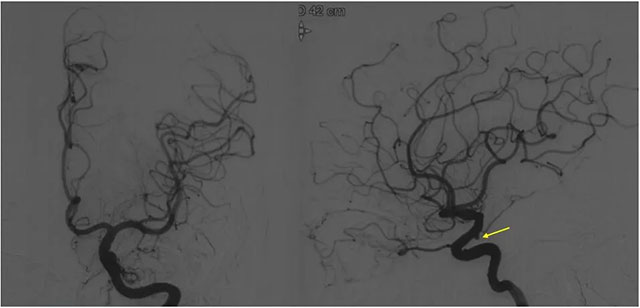

▲ DSA檢查顯示,左側(cè)竇區(qū)動(dòng)靜脈瘺

DSA 檢查顯示,左側(cè)竇區(qū)動(dòng)靜脈瘺,靜脈瘺術(shù)后改變,供血?jiǎng)用}為枕動(dòng)脈,通過皮層靜脈引流至橫竇,左側(cè)椎動(dòng)脈通過肌支供血匯入枕動(dòng)脈。